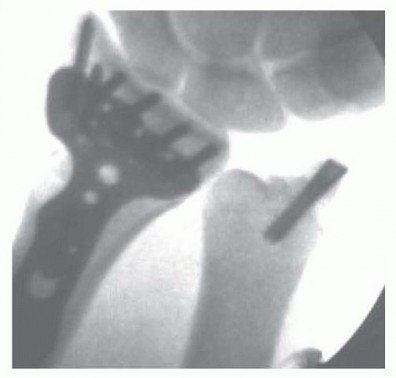

Apply a volar distal radius locking plate to stabilize the volar bone fragments ( TECH FIG 4B). Place a screw in the proximal portion of the plate first to reduce the plate to the shaft. Provisionally pin the distal fragments through the plate. Manipulate the articular fragments under fluoroscopy to obtain as anatomic a reduction as possible ( TECH FIG 4C,D). Suspend the wrist in the traction tower and reduce the articular fragments arthroscopically ( TECH FIG 4E,F). If articular reduction is not anatomic, remove the pins and fine-tune the reduction. Once the fracture reduction is thought to be anatomic, place the distal screws through the plate ( TECH FIG 4G-I). It is important that the fracture be reduced to the plate, with no gap between the plate and the bone. This can be achieved by flexion of the wrist in the tower and by insertion of a nonlocking screw first, before the insertion of standard locking screws. Place the remaining proximal and distal screws if the reduction is anatomic under both fluoroscopy and arthroscopy. 1. ### Reduction and Stabilization of a Dorsal Die-Punch Fragment It is not possible to see the reduction of a dorsal die-punch fragment through the volar approach when stabilized with a plate. Arthroscopy can be helpful in this scenario. Insert the volar plate as previously described and provisionally fix the device to the radius. Frequently, the dorsal fragment may still be slightly proximal in relation to the radial shaft. The dorsal die-punch fragment is best seen with the arthroscope in the 6R portal. Establish the volar radial portal between the radioscaphocapitate ligament and the long radiolunate ligament, as viewed directly through the previous performed volar approach. 23 Percutaneously elevate and anatomically reduce the dorsal diepunch fragment as viewed arthroscopically. Once this has been achieved, place the screws into the plate and observe their path arthroscopically to ensure adequate stabilization of the dorsal die-punch fragment. 2. ## Ulnar Styloid Fractures Following anatomic reduction of the distal radius fracture, insert the arthroscope in the dorsal 3-4 portal and the probe in the 6R portal. Palpate the tension of the articular disc. Good tension indicates that the majority of the peripheral TFCC fibers are intact or still attached to the proximal ulna. A peripheral tear of the articular disc is repaired arthroscopically when detected. 30 Stabilization of a large ulnar styloid fragment is considered when the articular disc is lax by palpation and no peripheral TFCC tear is identified ( TECH FIG 5). In this instance, the majority of the fibers of the TFCC are attached to the displaced ulnar styloid fragment. Make a small incision between the extensor carpi ulnaris and the flexor carpi ulnaris tendons and identify the fracture site. Retrieve the distal fragment, which often displaces in a distal and radial direction. Mobilize the styloid fragment using a no. 15 blade, taking care to protect the TFCC insertion. Reduce the fragment anatomically, under direct visualization, and insert a guidewire in a retrograde manner for provisional stability. Stabilize the ulnar styloid fragment using either a tension band technique (with wire and two K-wires) or, preferably, using a micro headless cannulated screw. Place the cannulated headless screw over the guidewire and verify fracture reduction with fluoroscopy. Insert the arthroscope into the 3-4 portal and the probe into the 6R portal to document restoration of TFCC tension.

TECH FIG 5 • In this case, following reduction to the distal radius fracture, the articular disc was palpated and found to be lax but with no peripheral tear. The large ulnar styloid fragment was reduced with a micro Acutrak screw.*